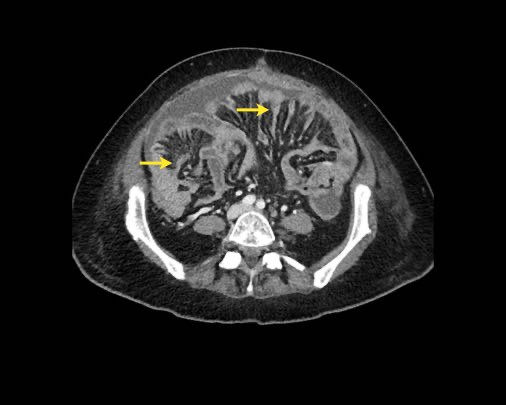

Hình ảnh

Hình ảnh CT của một bệnh nhân ung thư phúc mạc.

Một lượng nhỏ dịch cổ trướng hiện diện ở góc phần tư trước bên phải.

Các đường dày dạng nốt vuông góc với thành ruột được ghi nhận.

Hình ảnh này đại diện cho tổn thương xâm lấn mạc treo ruột lan rộng (mũi tên).